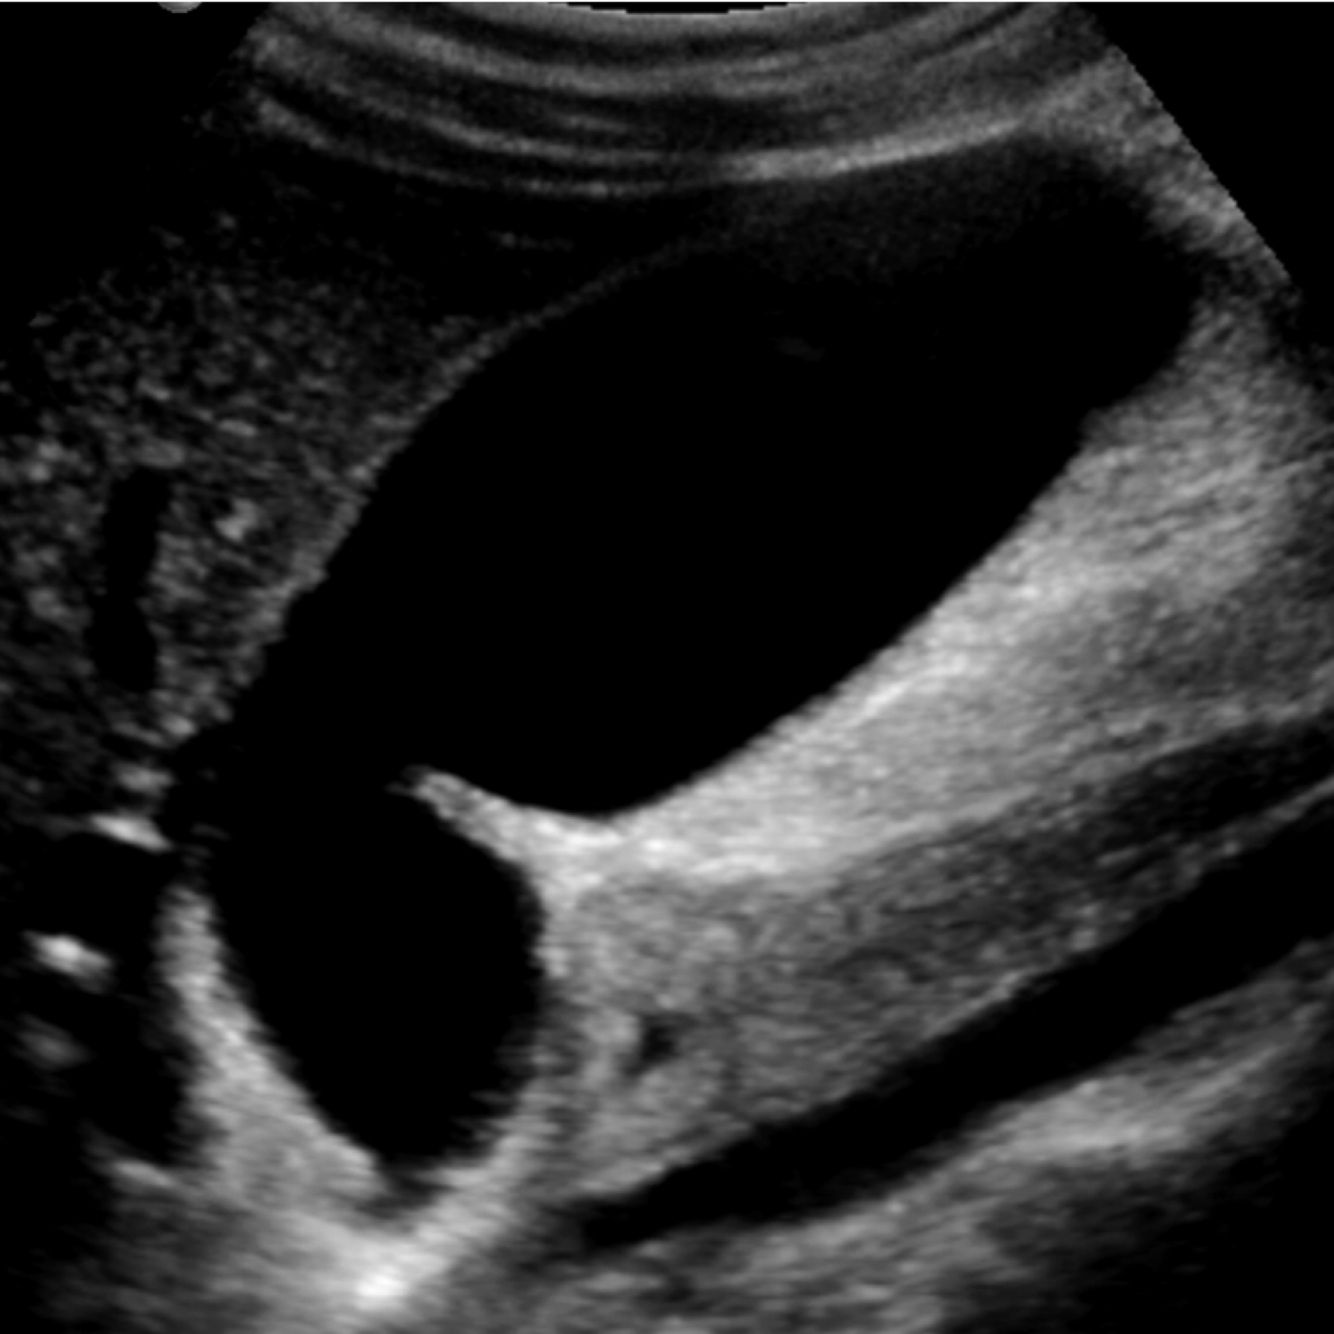

A

Wall-Echo-Shadow Triad

●With careful technique, visualize wall–echo–shadow (WES) triad or double-arc shadow sign.

●First arc or curved echogenic line represents thickened GB wall.

●Second arc is from surface of stone followed by posterior acoustic shadowing.

●With chronic disease, GB may be so contracted and is difficult to visualize.

●WES sign can be mimicked by residual barium, a porcelain gallbladder, or Bouveret syndrome.

●Air-filled bowel loops in RUQ may create shadowing which can be mistaken for contracted GB with stones.

●Differential diagnosis for chronic cholecystitis is adenomyomatosis and GB carcinoma.